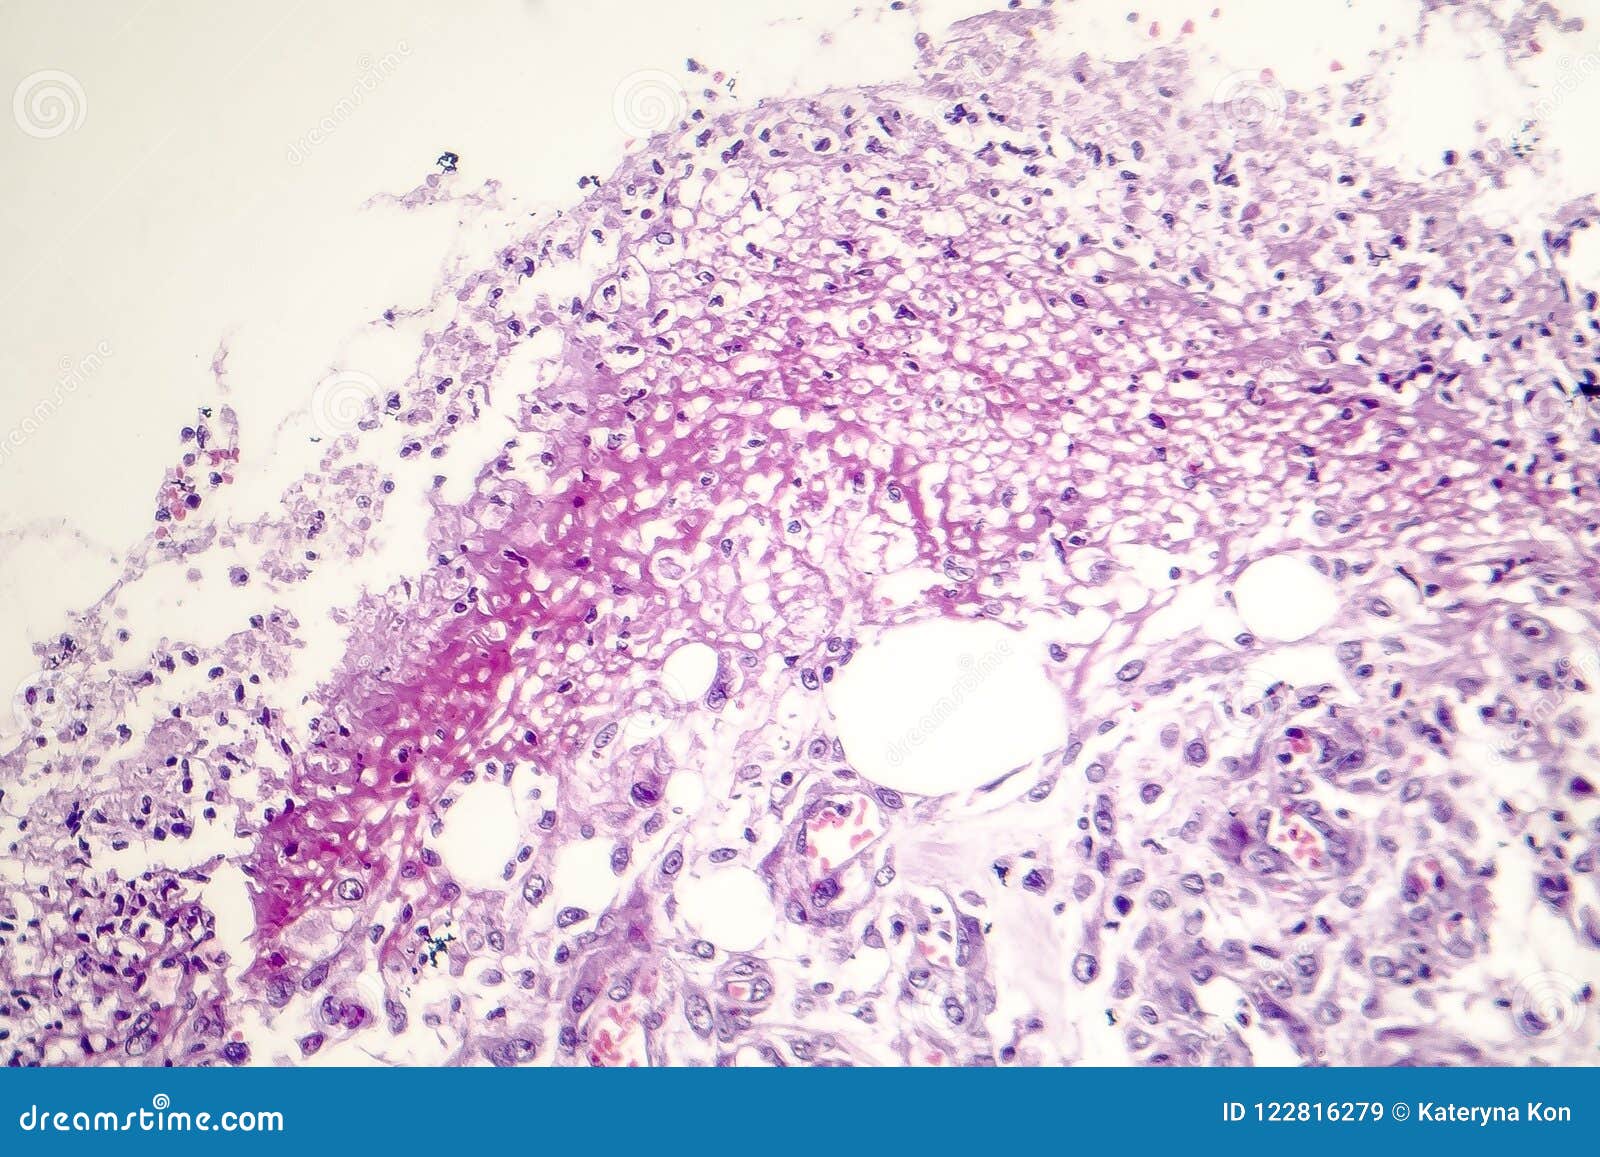

Язвенный колит толстой кишки